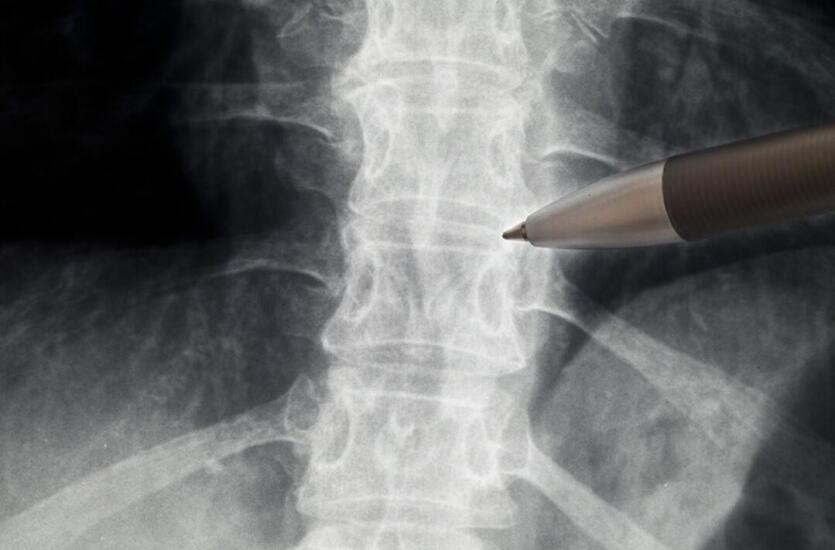

Współczesne metody diagnostyki wad postawy ciała mogą pozwolić na precyzyjne określenie problemów i doboru odpowiedniej terapii. Coraz więcej osób zdaje sobie sprawę z konieczności dbania o prawidłową postawę, co może przełożyć się na zdrowie kręgosłupa i ogólną kondycję organizmu. Warto zatem poznać różne metody badania postawy ciała, które mogą pomóc wykryć ewentualne wady i zapobiec ich pogłębianiu.

Pletyzmografia to metoda badania ruchomości kręgosłupa, która może pozwolić na ocenę jego funkcjonowania podczas wykonywania różnych ruchów. Badanie polega na założeniu pacjentowi specjalnych czujników, które rejestrują ruchy kręgosłupa w trakcie wykonywania określonych ćwiczeń. Pletyzmografia może pozwolić na precyzyjne określenie zakresu ruchomości kręgosłupa oraz wykrycie ewentualnych ograniczeń czy bólu podczas ruchu.